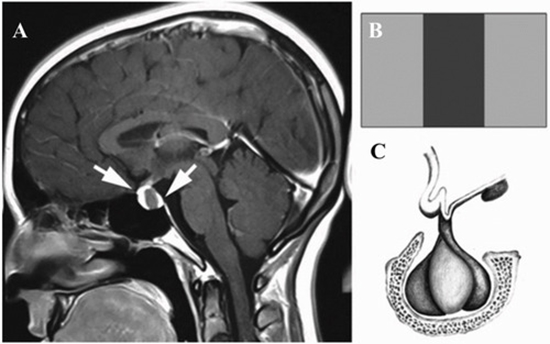

Vertical triband flag sign for differential diagnosis of Rathke’s cleft cyst

Results: There were 8 (19 %) males and 34 (81 %) females with a mean age of 37.2-years. Our study identified a distinct imaging characteristic in 38 of the cases, which we have named the "vertical triband flag sign", due to the growth of the cyst developing a specific appearance. The flag sign was mostly observed only in the T1-images (71.5 %), while in four cases the sign was spotted only in T2-images, and in four cases it appeared in both T1 and T2. In 4 cases, the flag sign was not observed in which further investigations revealed that these cases were suprasellar or small sellar RCCs. The dot sign, which is a characteristic finding in RCCs was only observed in one of our cases.

Conclusion: Early diagnosis of RCCs may be facilitated by utilizing the vertical triband flag sign.